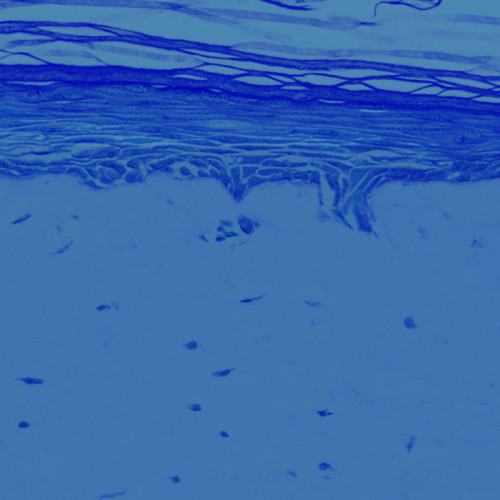

• The EpiDermFT™ (MatTek)

자세히 보기

• The EpiDerm™ (MatTek)